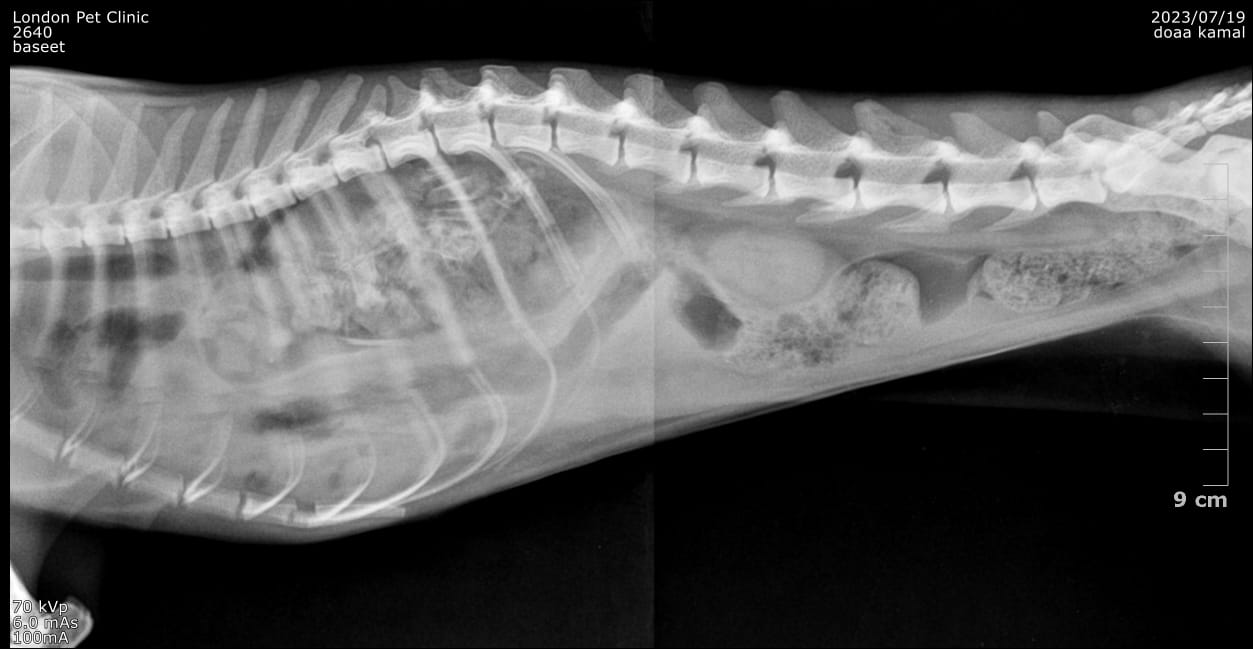

X-Ray after one week ..